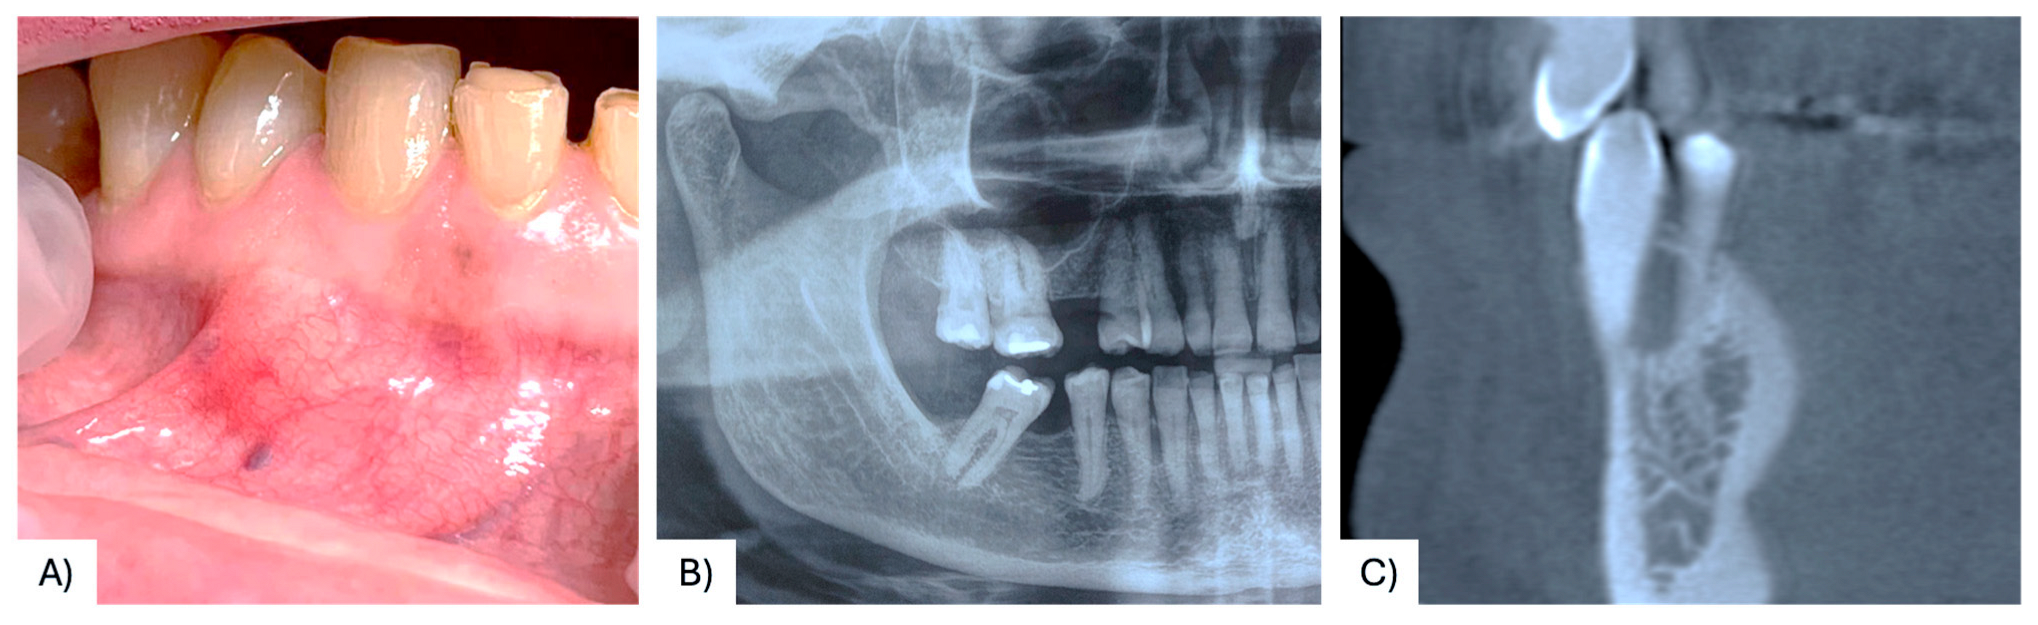

| 37 | Present case | 68 F | Maxilla, between #4.3, #4.4 | Asymptomatic nodule | 15 mm | Radiolucency with a defined margin area | Alveolar bone resorption | Excisional biopsy, curettage | No recurrence at 6 months follow-up | 2025 |